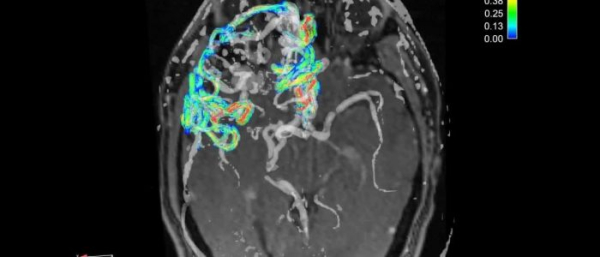

| Магнитно-резонансная томография (МРТ) | Применяются высокочастотные импульсы и мощные магнитные поля. Рентгеновские лучи не используются. Помогает обнаружить опухоли и другие патологии, отслеживает активность коры мозга. Высокая точность результатов. Метод имеет противопоказания. |

| Ангиография | Используется для установления патологий сосудов, обнаружения в них опухолей. Исследование проводится путем катетеризации через крупную артерию (бедренную, сонную). Однако метод не слишком успешен в определении именно гигромы. Имеет противопоказания. |